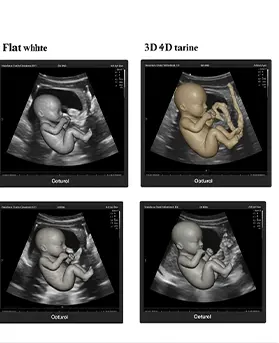

بينما يوفر السونار التقليدي (2D) معلومات أساسية هامة، فإن تقنيات 3D و 4D تأخذنا إلى مستوى جديد تماماً من الدقة. السونار ثلاثي الأبعاد (3D) يجمع سلسلة من الصور ثنائية الأبعاد لإنشاء صورة ثابتة ومجسمة للجنين. أما السونار رباعي الأبعاد (4D)، فيضيف عنصر الزمن، مما يتيح لنا رؤية هذه الصور المجسمة وهي تتحرك في الوقت الفعلي، كأننا نشاهد فيلماً قصيراً لطفلك وهو يبتسم أو يمص إصبعه.